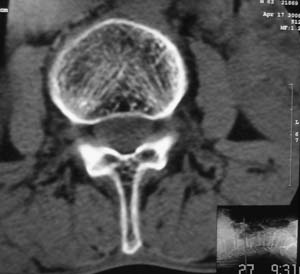

以下是引用余辉在2008-4-27 17:12:00的发言:[br]骨质疏松伴病理性压缩性骨折,椎骨骨松质密度减低,椎体骨小梁稀疏且普遍呈火柴头样改变,椎体无膨胀,无软组织肿块

以下是引用mzh123在2008-4-27 19:33:00的发言:[br]除压缩骨折表现外 还有许莫氏结节改变

以下是引用随光逐影在2008-4-27 21:29:00的发言:[br]除压缩性骨折外,还有许莫氏结节及骨质疏松表现。